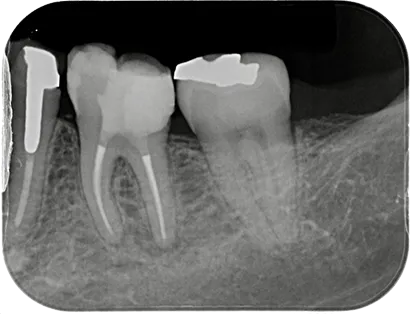

虫歯など様々な理由で歯の内部に細菌感染が広がることがあります。歯内療法(根管治療)とは、文字通り歯の内部の治療で、感染が広がった根管(神経が通る管)に対して適切な治療を行うことにより歯の機能を回復させることができます。

経験と技術が必要とされる

「歯の根の精緻な治療」により、

長期的な口腔内の健康維持を目指します。